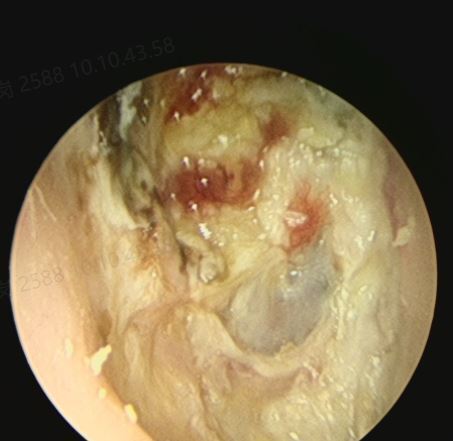

對于許多外耳道膽脂瘤的患者來說,門診的耳內(nèi)鏡清理一般就可以解決了。但是少部分嚴重的患者,門診沒辦法清理,一個是外耳道骨質(zhì)有明顯的擴大破壞,另一個是團塊比較硬,沒辦法直接拿出來。這時候就需要住院麻醉后再取膽脂瘤。最近就有一位張先生,40歲,多年的耳朵不適,最后確診外耳道膽脂瘤,嚴重影響正常的生活。檢查后發(fā)現(xiàn)膽脂瘤范圍大,外耳道明顯的擴大,外耳道清理非常困難。所以就住院全麻后進行外耳道清理。整個的過程非常的順利。術(shù)中看患者的鼓膜是完整,乳突氣房沒有暴露。清理干凈后結(jié)束了手術(shù),術(shù)后查房患者無明顯的不適,無手術(shù)相關(guān)的并發(fā)癥。對于外耳道膽脂瘤的患者,少部分嚴重的膽脂瘤,門診清理非常痛苦時,可以考慮麻醉后在清理。如果您還有什么問題,歡迎留言和耳鼻喉鄭立崗醫(yī)生進一步交流。

11歲的小王,10天前被家人發(fā)現(xiàn)雙耳有血性滲出液流出,由于學(xué)業(yè)比較緊張,家長周日才抽時間來到佛山復(fù)星禪誠醫(yī)院找到耳鼻喉鄭立崗主任就診。鄭主任讓他做個耳內(nèi)鏡清理看看出血的原因,結(jié)果是雙側(cè)巨大外耳道膽脂瘤。由于范圍太大,清理起來孩子痛的受不了,就入院了。住院全面評估后發(fā)現(xiàn)孩子的外耳道膽脂瘤確實非常的嚴重,雙側(cè)的外耳道都擴大了,右側(cè)還并發(fā)了許多的肉芽組織。梅曉峰主任、鄭立崗主任帶領(lǐng)的耳鼻喉團隊在認真分析患者病情后建議行全麻耳內(nèi)鏡雙側(cè)外耳道膽脂瘤清除,術(shù)中需注意保護鼓膜及外耳道的皮膚。手術(shù)由鄭立崗主任和劉蘭花醫(yī)生主刀,術(shù)中發(fā)現(xiàn)右側(cè)外耳道由于破壞嚴重有大量的肉芽組織,左側(cè)的外耳道以膽脂瘤為主。整個的手術(shù)完整保留了鼓膜和外耳道皮瓣,用時約40分鐘,非常的順利。術(shù)后查房患者感覺良好,無明顯的不適及手術(shù)并發(fā)癥。對于外耳道膽脂瘤,其實主要是小朋友階段沒有定期的清理外耳道耵聹和脫落的上皮組織導(dǎo)致的,耳鼻喉醫(yī)生一般建議在10歲之前最好每年來醫(yī)院耳內(nèi)鏡清理外耳道耳屎一到兩次。由于許多家長和孩子平時比較忙,沒時間來醫(yī)院清理。佛山復(fù)星禪誠醫(yī)院耳鼻喉多年來一直在周六、日正常開展耳鼻喉的各種內(nèi)鏡檢查(耳內(nèi)鏡、鼻內(nèi)鏡、電子喉鏡及聽力、耳石復(fù)位等),方便大家。佛山復(fù)星禪誠醫(yī)院耳鼻喉團隊在梅曉峰主任(耶魯大學(xué)博士后)和鄭立崗主任(2016中國耳鼻喉十佳好大夫)兩位學(xué)科帶頭人的帶領(lǐng)下,堅持通過創(chuàng)新來不斷提高療效,使科室在耳鼻喉疾病的特色治療方面走在了全國前列,每年都有許多來自全國各地的患者慕名前來。